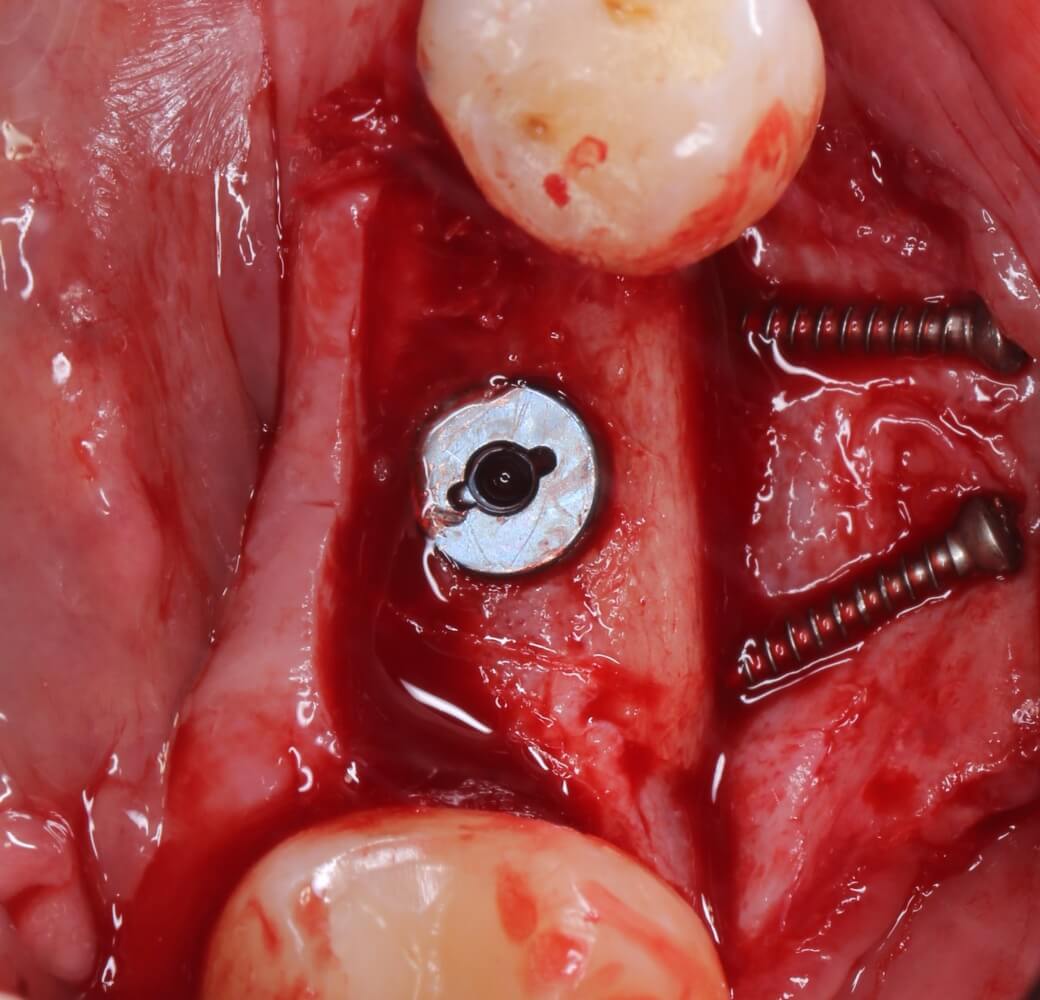

Кстати, обрати внимание на ширину альвеолярного гребня (левая картинка). Она чуть меньше 3 мм. Это объясняет, почему я засомневался в возможности установки имплантатов одновременно с остеопластикой. Понятно и без КЛКТ.

Возвращаемся к основной операционной области. Еще раз посмотрим на альвеолярный гребень, поофигеваем от его ширины и моих грандиозных планов:

Я зафиксировал костный блок практически без адаптации на несколько винтов. Обрати внимание, что винты находятся в зоне, где не планируется установка имплантатов. Фиксация должна быть надежной, поскольку мне еще предстояла подготовка лунок для имплантатов. Трех винтов для этого вполне достаточно.

Глянем на то, что получилось: